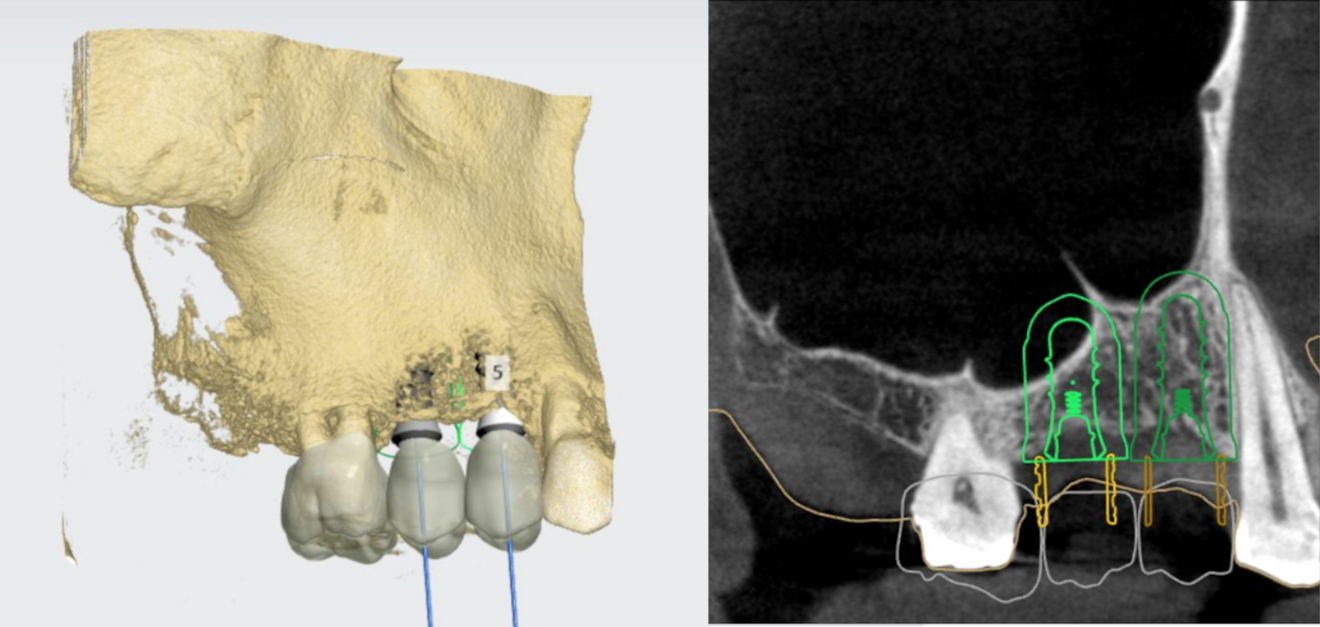

The prosthetic restorations were first designed in planning software (Implant Studio, 3Shape). The DICOM volume data set (from the CBCT scan) was then merged with the STL surface data set (from the intra-oral scan; Fig. 2), and the implants were aligned on the basis of the prosthetic restorations (Fig. 3).

Fig. 2: Merging of the DICOM volume data set with the STL surface data set.

Figs. 3a & b: Alignment of the implants on the basis of the prosthetic restorations.

The vertical dimension in region #14 was 10.5 mm and decreased distally from 5 mm to 7 mm in region #15. Straumann Standard Plus implants were planned for region #14 (3.3 × 10.0 mm) and region #15 (4.3 × 8.0 mm). The use of implants of these lengths would require an internal sinus lift.

In order to allow guided preparation of the osteotomy to just before the maxillary sinus and the Schneiderian membrane, implant #15 was moved coronally in the planning software and its length shortened. The planning was completed with the creation of the surgical guide and the corresponding drilling protocol.